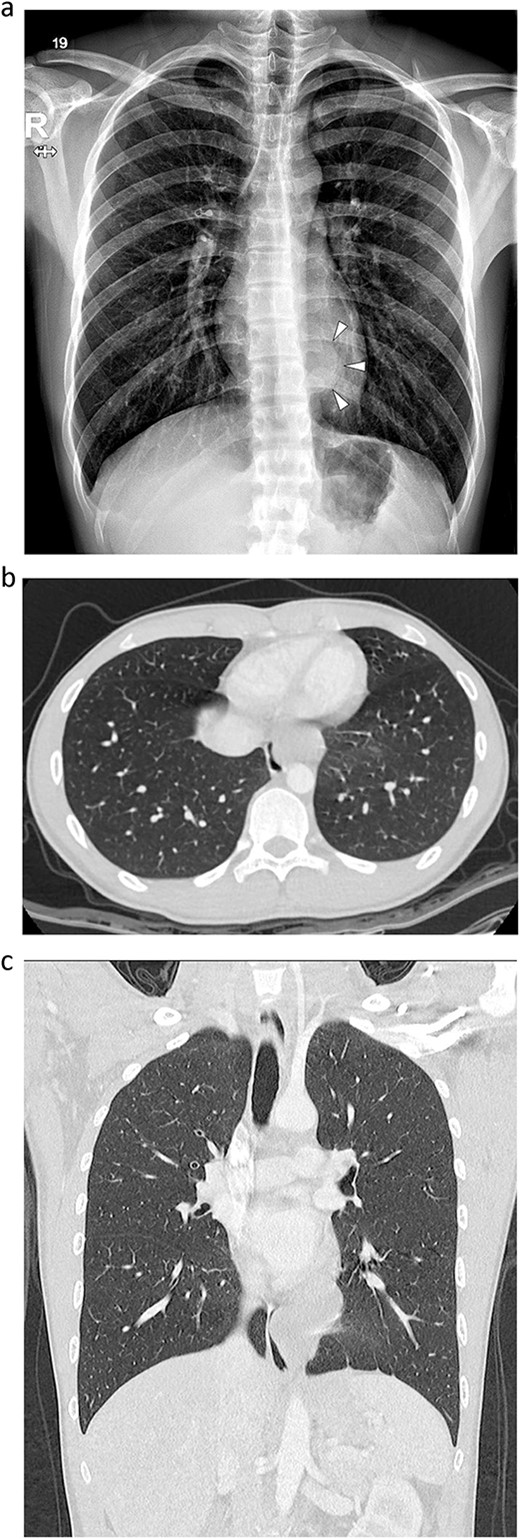

An 18-year-old male patient presented to the emergency department with right-side chest pain of 1-day duration. A plain chest x-ray confirmed a right pneumothorax. A tumor in the left lower paravertebral area was suspected (Fig. 1a). A CT of the chest was performed and showed a 6-cm large, well-defined, probable cystic mass in the left posterior mediastinum, adjacent to the esophagus. Esophageal duplication or bronchogenic or neurenteric cyst was suspected (Fig. 1b and c). The patient was discharged after pneumothorax had improved. Two months later, he was readmitted for surgery to remove the cystic tumor. Single-incision video-assisted thoracoscopic surgery (VATS) was performed to treat the posterior mediastinal tumor. The patient was placed in the prone position. An incision of 4 cm in length was made in the left ninth intercostal space at the lateral line of the scapula. A 5-mm thoracoscope with a 30-degree view was used. A cyst was identified in the posterior mediastinum (Fig. 2a), and a longitudinal incision was made in the mediastinal pleura. The left vagus nerve was placed beside the tumor. The lower half of the cystic mass was embedded in the muscular layer of the esophagus (Fig. 2b) and was in contact with the esophageal mucosa. The cyst was dissected carefully from the surrounding tissue. During dissection, the cyst ruptured, discharging an ivory mucoid creamy fluid. The cyst was completely removed with no injury to the esophageal mucosa. The esophageal mucosa, which was in close contact with the cyst, was stretched and protruding. To cover the exposed esophageal mucosa, the dissected esophageal muscle and periesophageal tissue were approximated with a continuous suture using a barbed suture (V-Loc™ 90, Medtronic) (Fig. 2c). Another barbed suture was used to repair the mediastinal pleura. A 24-Fr chest drain tube was placed through the same port (Fig. 2d). The operation took 80 min. The patient’s diet was started on the evening of the surgery. The chest drain was removed on the 1st postoperative day, and the patient was discharged from the hospital on the 2nd postoperative day without problems. Histopathological examination revealed a bronchogenic cyst. A CT scan of the chest carried out 2 years 7 months after the operation and confirmed that the patient had healed without any complications (Fig. 3).

A computed tomography scan at 2 years 7 months after surgery. There was no evidence of tumor recurrence.